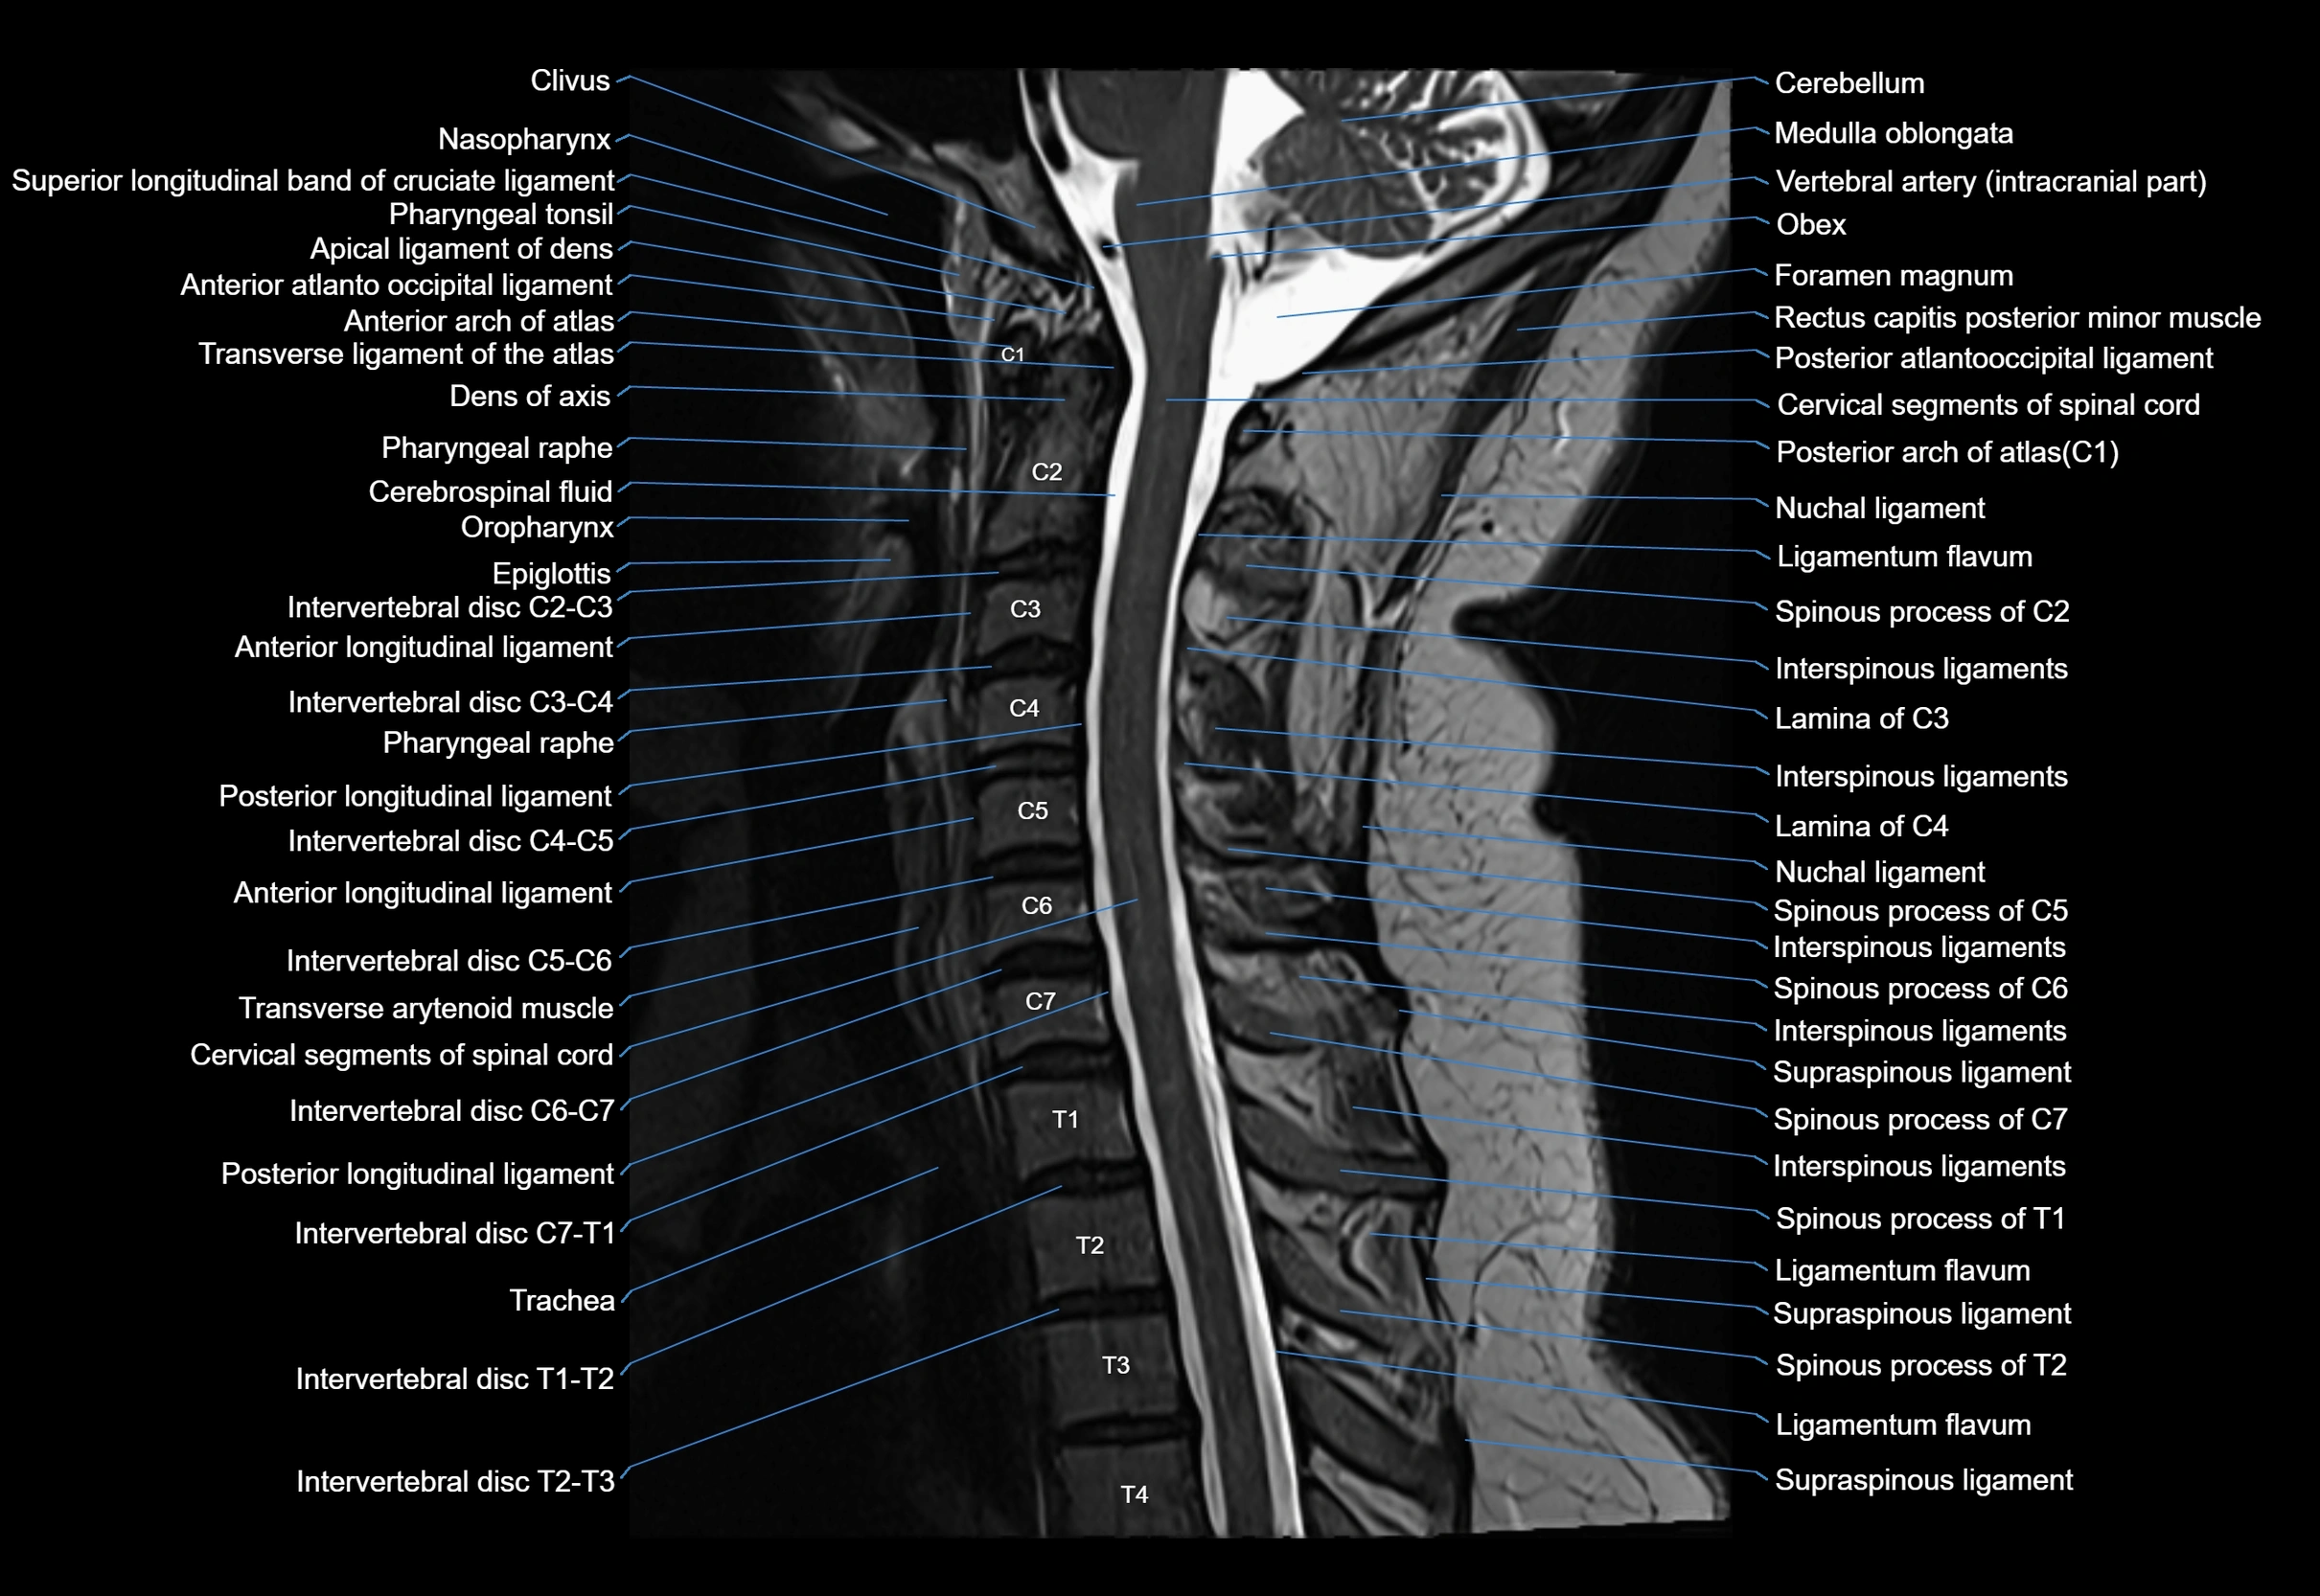

MRI appearance

T1-weighted images:

• Annular epiphysis: Low signal cortical rim at the vertebral margin

• Adjacent marrow: Intermediate-to-high signal in the vertebral body

• Disc interface: Clear delineation between bone and annulus

T2-weighted images:

• Annular epiphysis: Low signal intensity line

• Endplate cartilage (in younger patients): Intermediate signal

• Intervertebral disc: High signal nucleus pulposus

STIR:

• Annular epiphysis: Low signal cortical rim

• Adjacent marrow: Suppressed fat signal with preserved bony outline

• Utility: Highlights marrow and endplate interface in developing spine

MRI image

image